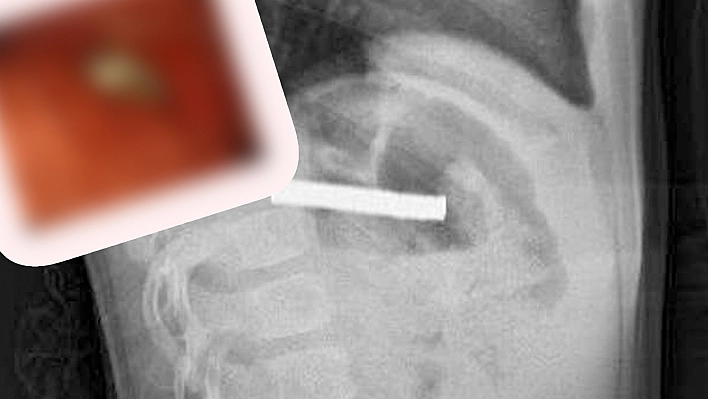

Elazığ'da 3 yaşındaki bir çocuğun yuttuğu 19 mıknatıs, Fırat Üniversitesi Hastanesinde başarılı bir operasyon ile çıkartıldı.

Edinilen bilgiye göre, Erzurum’da bir çocuk evde bulunan 19 tane mıknatısı yuttu. Çocuğun rahatsızlanması sonucu durumu öğrenen aile hastaneye başvurdu. Daha sonra çocuk Elazığ’a sevk edildi. Fırat Üniversitesi Çocuk Gastroenteroloji Hepatoloji ve Beslenme Bilim Dalı Başkanı Prof. Dr. Yaşar Doğan, çocuk hastanın yemek borusuna yapışmış 19 mıknatısı endoskopik yöntemle çıkardı.